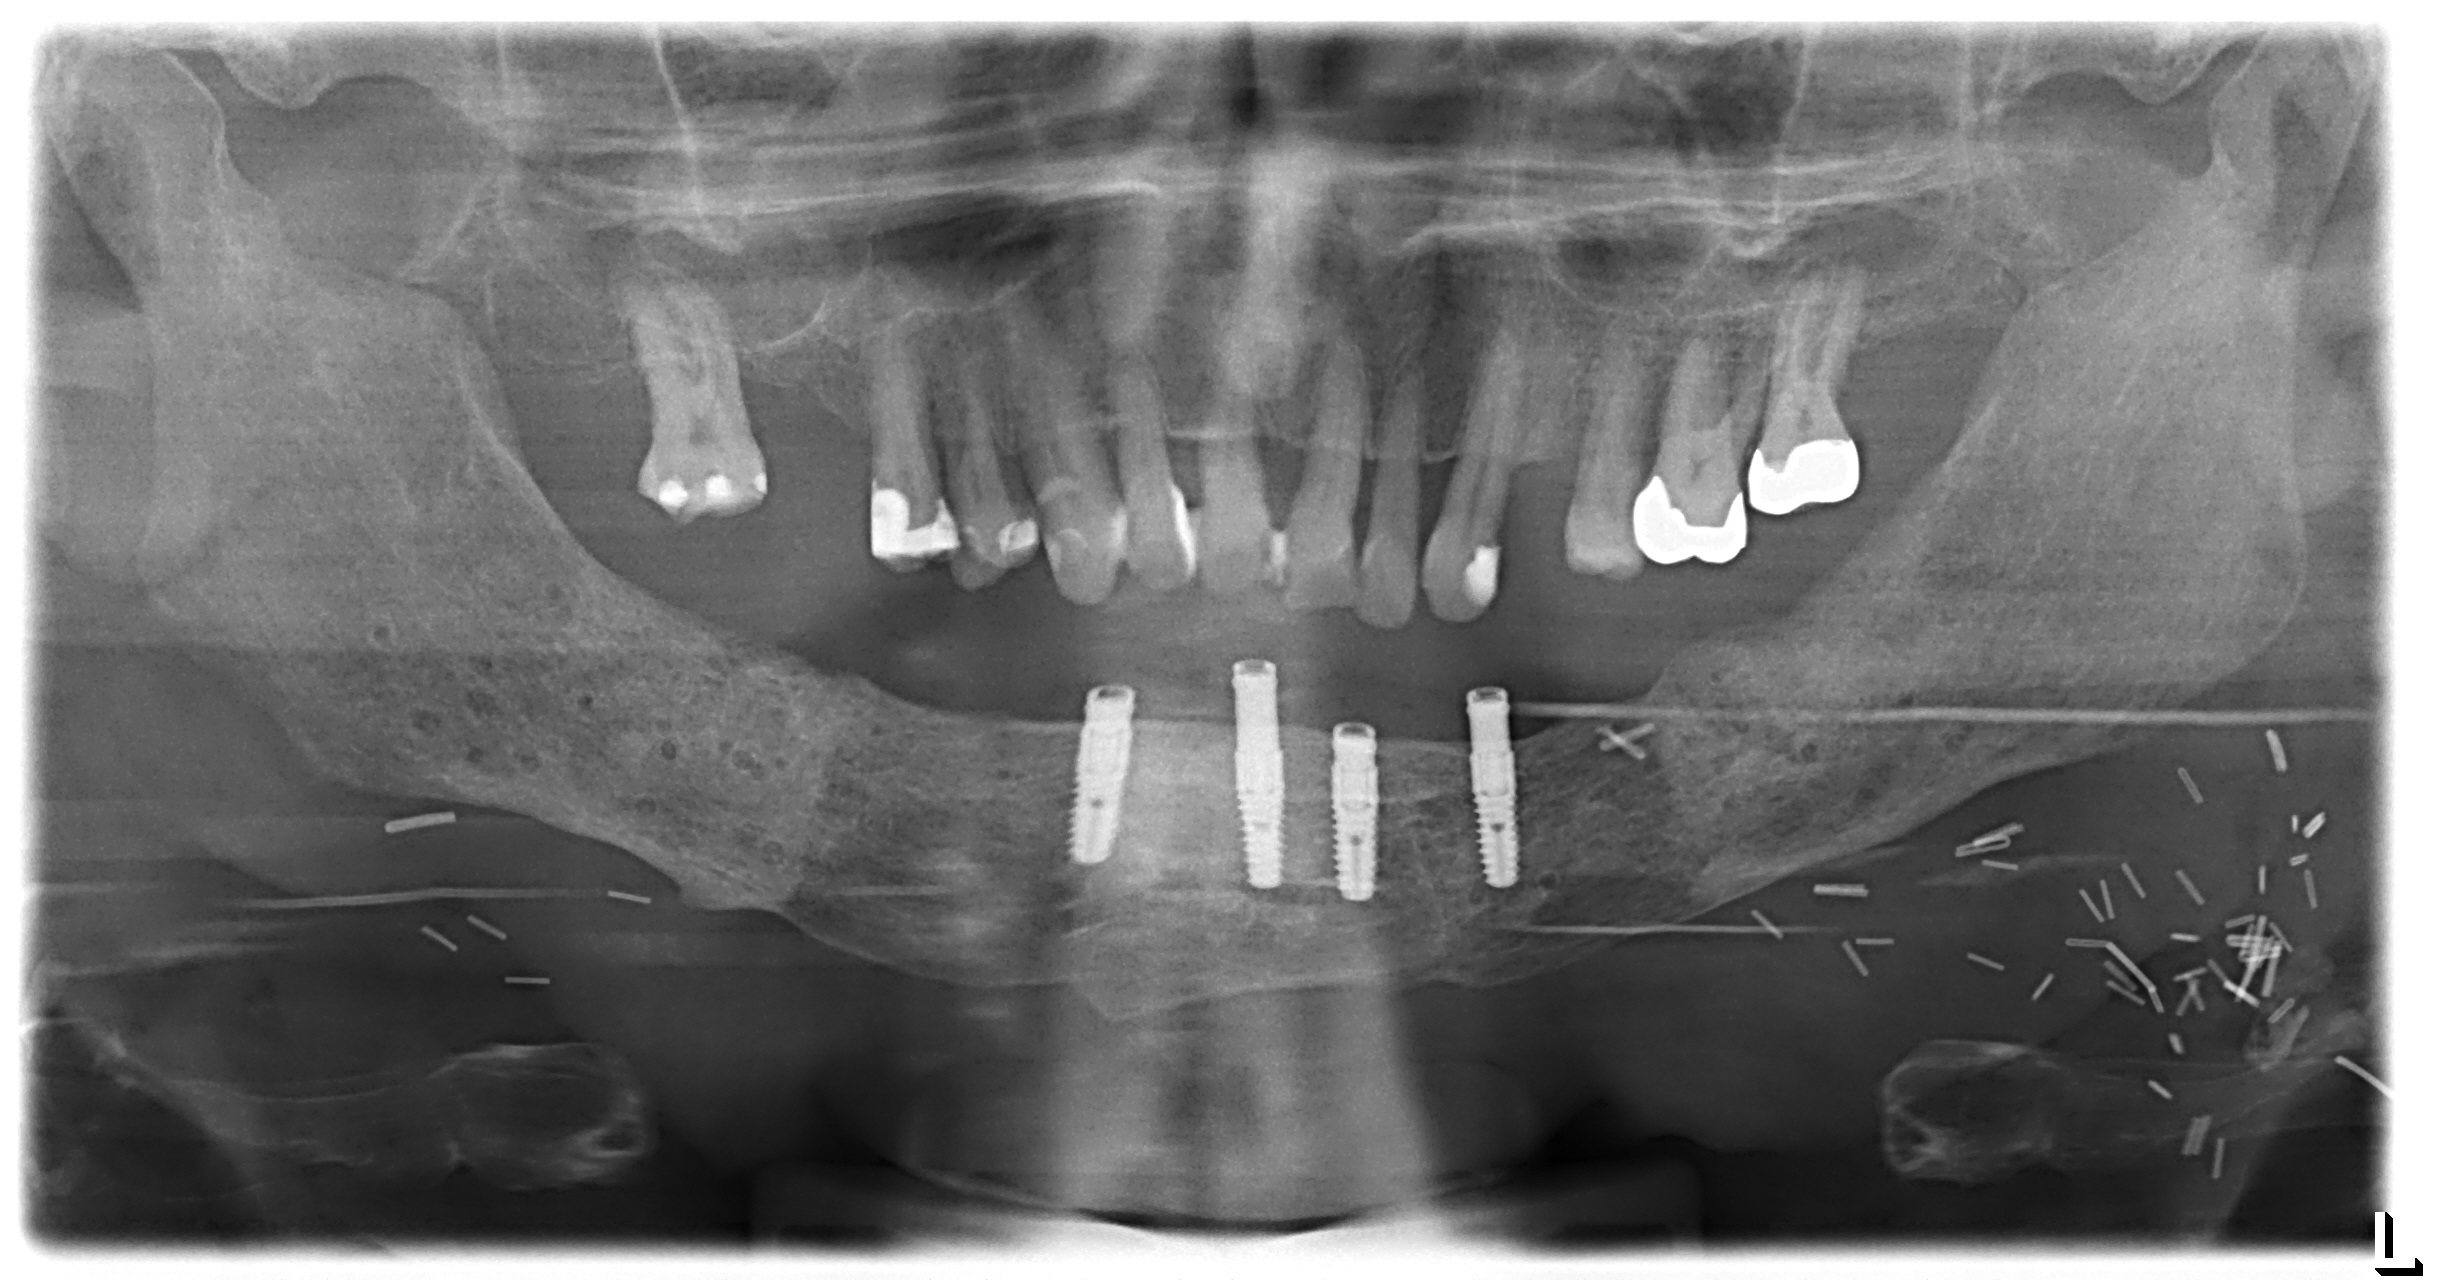

Postoperative imaging confirmed minimal intersegmental gaps to the mandibular remnants with undisturbed healing but limited overall bone volume (Fig. 7a-c). Therefore removal of the PSPMP and a preimplantological augmentation with corticocancellous iliac bone grafts followed 16 months later.

Finally, dental implants were inserted (Fig. 8).